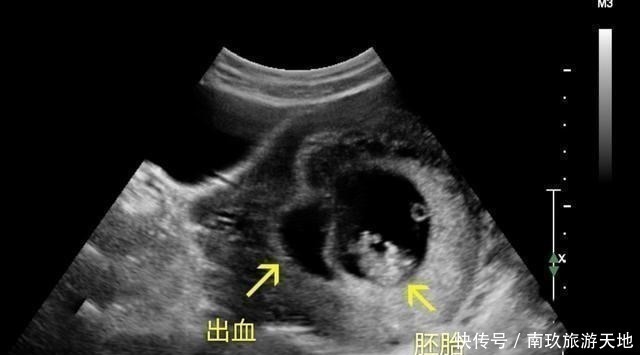

征兆2. 见红在孕早期,孕妈最怕的就是发生先兆流产,而发生先兆流产时,往往以见红作为主要症状。当然,不一定是鲜红色的血,还可能是出现褐色分泌物,但不管哪种,只要出现,最好都去医院检查检查血HCG和孕酮的情况、做B超看看胎儿的宫内发育情况,是否发生胎停的情况,若还没出现胎心,听医生的建议就好。征兆3. 腹痛腹痛和见红往往会伴随出现,但也有的孕妈在孕早期仅以腹痛为主要,这是因为出现了宫缩引起的,这是不正常的表现,如果宫缩非常频繁(肚子剧烈疼痛),孕妈要特别的引起重视,要及时去医院,检查看看胎儿在宫内的发育情况。